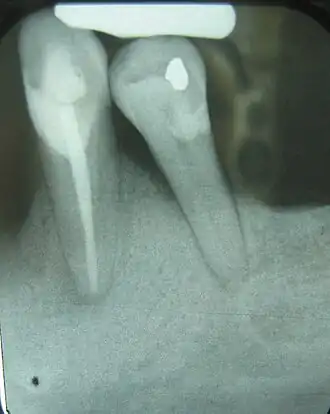

Horizontal defects

Generalized bone loss occurs most frequently as horizontal bone loss.[2] Horizontal bone loss manifests as a somewhat even degree of bone resorption so that the height of the bone in relation to the teeth has been uniformly decreased, as indicated in the radiograph to the rig defects occur adjacent to a tooth and usually in the form of a triangular area of missing bone, known as triangulation.[2]